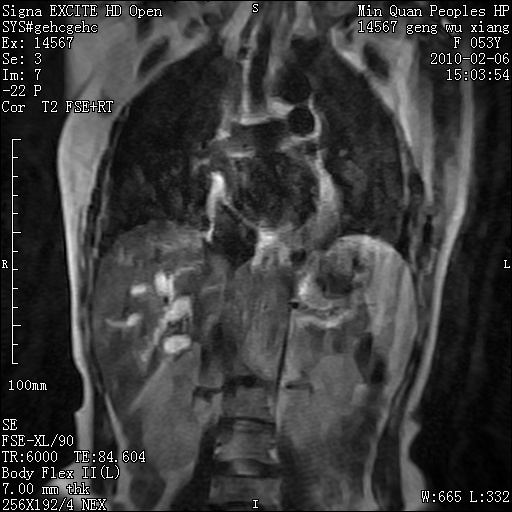

标题: MRI2762:胆道梗阻原因?

f,53y,全身黄染多日。

高位胆道梗阻 胆管癌可能性大

支持 高位胆道梗阻 胆管癌可能性大。